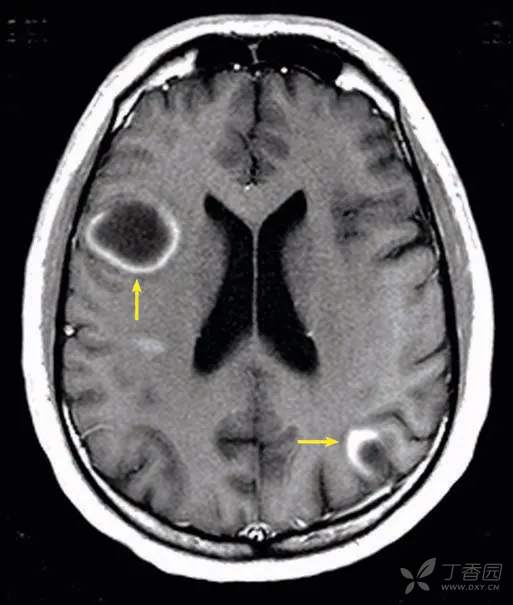

表现

轴位MRT1增强图像显示多发强化病变,包括右额叶、左顶叶。这些曲线样强化,在边缘处中断。

鉴别诊断

• 脱髓鞘疾病

• 原发性肿瘤

• 淋巴瘤

大约一半的肿瘤性脱髓鞘病变表现出病理性增强。“不完整环”增强是一个相对特异性的征象,有助于鉴别急性脱髓鞘(尤其是多发性硬化症)与感染和肿瘤病因。增强部分代表脱髓鞘的活性(前沿)边缘,并向白质延伸。非增强部分代表脱髓鞘的无活性(尾部)边缘,指向灰质或基底神经节。也可出现中央不增强的核心,与神经胶质增生的慢性炎症有关。可出现血管源性水肿,尤其是在活动性疾病区域。脑环形强化病变的一般记忆符号为“ MAGIC DR L”:转移,脓肿,多形性胶质母细胞瘤,梗塞(亚急性),挫伤,脱髓鞘疾病,放射坏死和淋巴瘤。除脱髓鞘疾病外,在免疫功能低下的患者中,低级别的原发性肿瘤和淋巴瘤中偶尔会出现“不完整环”样增强。